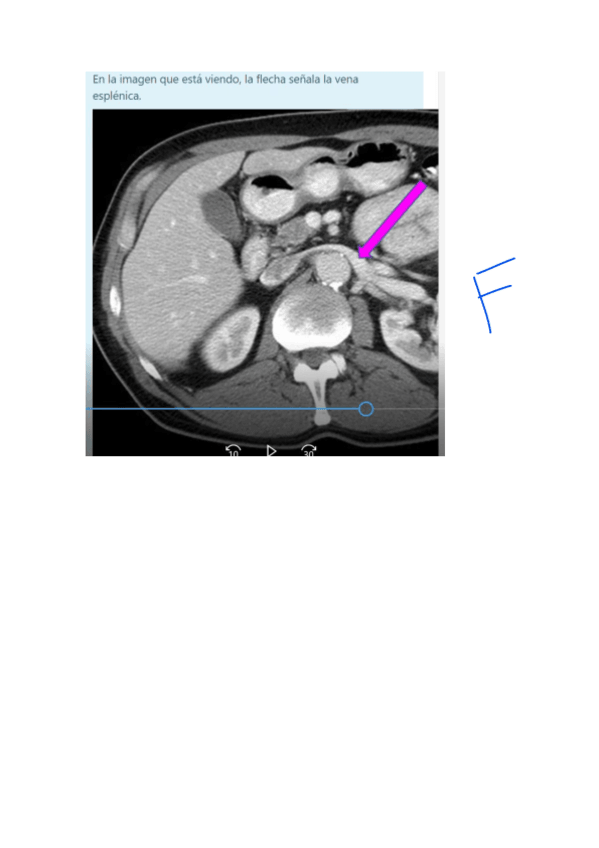

Practicas-12-y-13-resueltas-con-nombres.pdf